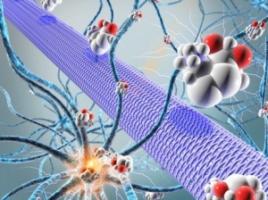

ÉPILEPSIE: Des neuroprotecteurs de la plasticité cérébrale